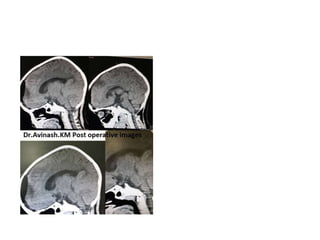

FIGURE 4. The capsule of the cystic craniopharyngioma was firmly attached to the left

hypothalamus, the stalk was dislocated to the right side (Patient 6). The outgrowth of the

craniopharyngioma from proximal stalk is recognizable A. Complete removal of the capsule was

possible, but produced subpial blood injection over the left hypothalamic surface B. MRI scan

revealed a small ischemic injury in the left hypothalamus C. This patient had transient sleep

disorder, moderate hyperphagia and memory problems (see also a supplemented video

material 1).